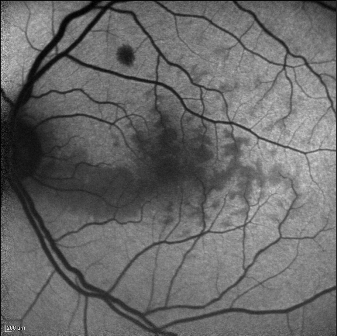

Fundus Autofluorescence

Fundus autofluorescence can detect a perivenular hypoautofluorescence with a fern-like appearance in patients with recent-onset CRVO.

This appearance is due to the masking of the normal autofluorescence from ischemic edema. In the retina, tissue transparency is a clinical index of tissue oxygenation. With CRVO, the most sensitive tissue for manifesting decreased oxygenation will be perivenular, and especially in the posterior pole, where oxygen use is higher than in the retinal periphery. The perivenular location of ischemic edema is due to decreased arterial flow that leads to preferential oxygenation of the periarterial retina, which uptakes the available oxygen and subsequently desaturates hemoglobin before it can reach the perivenular space. This will manifest as patchy ischemic retinal whitening, located preferentially in a perivenular distribution near the macula.[10]